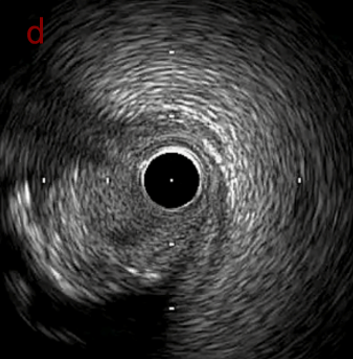

IVUS after OAS high speed 3回

IVUS imaging after high speed 3回

a,b,cはさらに石灰化に食い込み、石灰化量は減少。

それに伴いdではbiasがさらにtentingのIVUS所見にへんかしhigh injury riskと思われた。

引き続き造影で確認してpinpointで引きのOAS high speedを3回さらに追加のためcでIVUSマーキングを行い、その点より引きで赤線のpinpoint OAS high speedを行い、dに関してはinjury回避のためにOASを当てない方針とした。